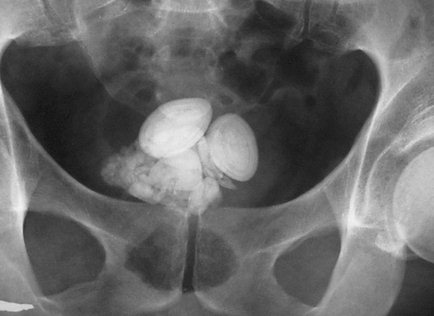

Поскольку симптомы нейрогенного мочевого пузыря схожи с симптомами нарушений мочеиспускания при воспалительных заболеваниях мочеполовой системы, проводится полное обследование органов этой системы на наличие инфекции. Это лабораторное исследование мочи с применением различных функциональных проб (по Зимницкому, по Нечипоренко и др.). Также поводится обследование органов мочеполовой системы с помощью методов медицинской визуализации (УЗИ, МРТ, цистоскопия, рентгенологическое исследование с применением рентгенконтрастных веществ) для обнаружения симптомов воспаления или аномалий строения мочевыводящих путей. Только полностью исключив воспалительный процесс, можно говорить о нейрогенном мочевом пузыре.